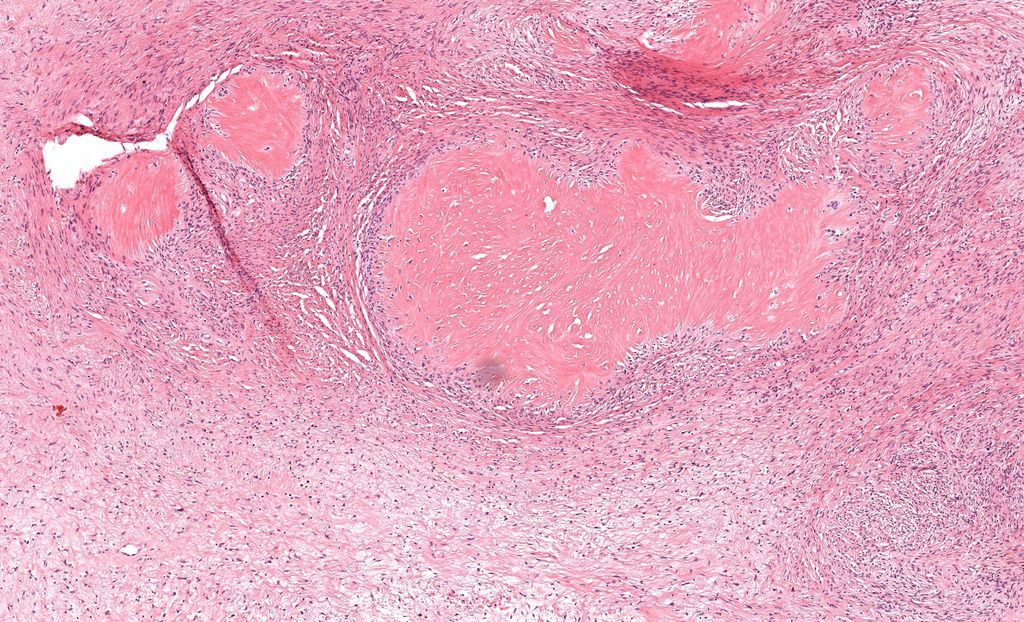

40 F. 10 cm deep thigh mass.

Answer ✅ youtu.be/QDb68_G1HR4?si…

Digital slide 🔬 kikoxp.com/posts/11800.

Differential dx: kikoxp.com/posts/12124

#BSTpath #pathologists #pathology #pathTwitter